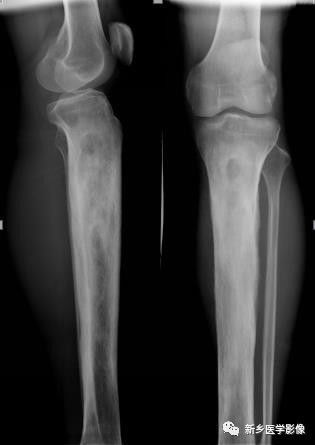

骨骼变形X线图像

膝部正位片示股骨下端与胫、腓骨上段膨大、变形,内部不规则泡状分隔